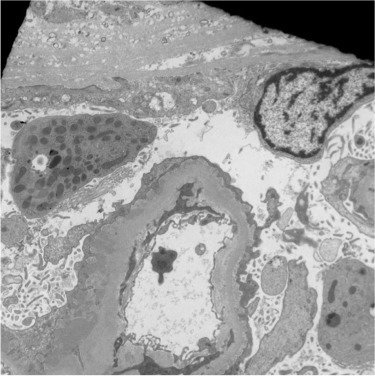

Glomerular Histiology

Renal Corpuscle

Filtration Barrier

Mesangium